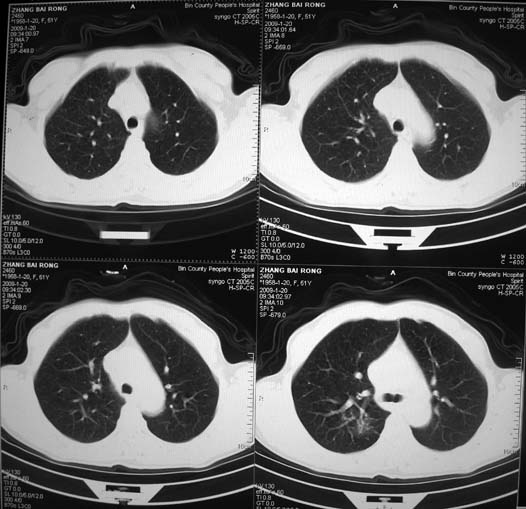

以下是引用zsl6918在2009-1-20 17:30:00的发言:[br]支持右肺下叶背段周围型肺癌,隆突下淋巴结肿大

以下是引用宇宙ct在2009-1-20 16:28:00的发言:[br]周围性肺癌\\纵隔淋巴转移

以下是引用sos.la在2009-1-20 18:01:00的发言:[br]实质性密度均匀肿块.边界清晰,浅分叶.无明显毛刺征,离胸膜近却无胸膜凹陷征,发生在段及段以下支气管,病灶直径远远超过此位置支气管管径而无阻塞征象,7#淋巴结肿大,病理是小细胞未分化癌(局限期)可能性最大.